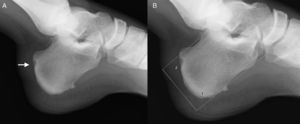

En la radiografía lateral (fig. 1) se apreciaba una prominencia de la tuberosidad posterior del calcáneo, que tras realizar varias mediciones se clasificó como deformidad de Haglund, y una lesión lítica en la cortical de su superficie posterior. En la RM (fig. 2) se visualizó una bursitis retrocalcánea, engrosamiento del tendón aquíleo, con una hiperintensidad de señal lineal intratendinosa en secuencia de supresión grasa, indicativa de rotura parcial, y aumento de intensidad en la región posterior del calcáneo en la misma secuencia, compatible con edema óseo. Estos hallazgos se clasificaron como síndrome de Haglund, diagnóstico que se confirmó quirúrgicamente.

La deformidad de Haglund es una alteración en la morfología del calcáneo, que forma una prolongación ósea vertical en la tuberosidad posterosuperior. Aunque se han propuesto varios criterios de medida para diagnosticarla, el método más usado es el de las líneas de inclinación paralelas (parallel pitch lines, PPL). Consiste en trazar una línea tangente a la superficie inferior del calcáneo, y otra paralela a ésta en la cara superior, a la altura del punto más alto de la cara posterior de la superficie de la articulación subastragalina3. Si la tuberosidad supera esta línea se puede considerar deformidad de Haglund2.